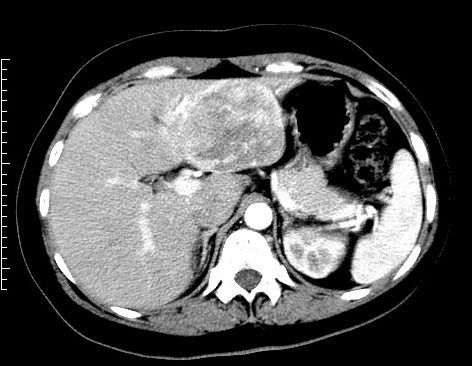

肝臟血管瘤怎么確診?

目前超聲是常用的體檢手段,患者的肝臟血管瘤多是由超聲檢查發(fā)現(xiàn)的。但普通超聲檢查有一定的局限性,有時(shí)難以明確病灶性質(zhì)是否為血管瘤,仍需進(jìn)一步檢查增強(qiáng)的影像學(xué)檢查,如:增強(qiáng)CT、增強(qiáng)核磁或是造影超聲。

經(jīng)過增強(qiáng)影像學(xué)檢查確認(rèn)為肝臟血管瘤后,可以定期通過超聲檢查,觀察病灶的大小變化即可,而不用每次復(fù)查都做增強(qiáng)影像。